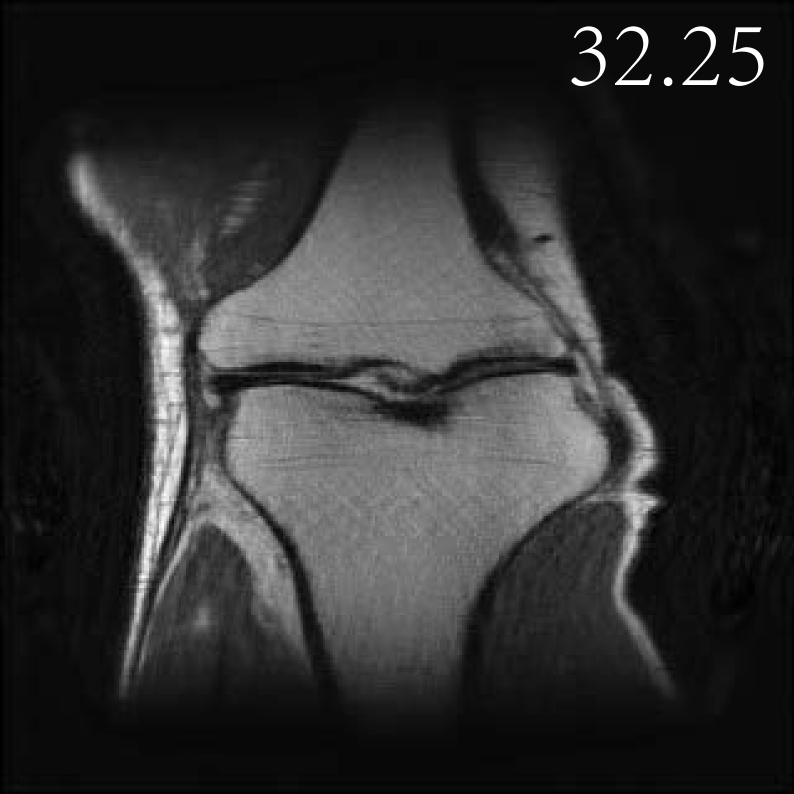

4.2.3 Accelerated Multi-coil MRI

In this subsection, we report the comparative performance of EI, SkEI and C-SkEI in multicoil MRI reconstruction task. We evaluate the performance of two distinct Sketched-EI methods proposed in this study for multicoil MRI, using a knee MRI image with 15 coils from zbontar2018fastmri . Subsequently, we performed a comparative analysis of the reconstruction results under two distinct sketch schemes and varying sketch sizes. Consistent with Section 4.2.1, we begin by comparing our proposed methods with the vanilla DIP method, considering the same DIP network architectures as outlined in Section 4.2.1.

For SkEI and C-SkEI schemes, SS is defined as the sketch operation that samples N15N\leq 15 coils from the original 15 coils, then forms a minibatch named ASNA_{S_{N}}. However, these two sketch schemes differ in their minibatch partition strategies. Specifically, as described in Algorithm 3, Coil-Sketch compresses the initial 15 coils and then selects the first LL compressed virtual coils as the new multi-coils. Subsequently, the first RR higher-energy virtual coils are retained, while the last SS lower-energy virtual coils undergo sketch operation. In contrast, Classical-Sketch directly acts on the original 15 coils, randomly sampling the NN coils into a minibatch. During each iteration, the minibatch is randomly chosen from the 15 coils for updates. For this study, we experiment with N=10,5N=10,5 and 22, respectively.

The visualized comparisons are shown in Figure 9, as can be seen, the performance of the DIP method is still suboptimal, consistent with findings from the sparse view CT experiments. In comparison, the EI method achieves remarkable improvements in reconstruction quality due to the EI regularizer. Furthermore, the reconstruction results generated by these two proposed sketch methods exhibit almost no loss in performance and even surpass the vanilla EI method. Furthermore, as presented in Figure 11 (b), the time cost per iteration of the sketched EI decreased compared to the vanilla EI method. Specifically, C-SkEI-2coils decreased 19% per iteration compared to vanilla EI, while SkEI-2coils (with subsampling sketches) decreased 17%. Moreover, we observe that C-SkEI demonstrates a much faster convergence rate compared to that of standard EI.

Refer to caption

AyA^{\dagger}y

DIP

*EI-full (15coils)

SkEI-5coils

C-SkEI-5coils

xx (GT)

Figure 9: Multi-coil MRI Images (with corresponding PSNR) reconstructed by DIP, EI and our two Sketched EI methods, where ‘SkEI-’ shorts for classical-sketch and ‘C-SkEI’ for coil-sketch. ‘*’ denotes the baseline.

Next, we investigate the performance of our proposed SkEI and C-SkEI in Test Time Training task. Specifically, we fine-tune the model trained on the fastMRI knee dataset in darestani2022test , with the experimental results illustrated in Figure 12. As we can see, the single measurement was corrupted by Gaussian noise with noise level σ=0.005\sigma=0.005, and the visualized images indicate that, in both the full-parameter Test Time Training (TTT) and Test Time Training with BatchNorm only (TTT-BN) scenarios, our proposed method yields reconstruction results that remain comparable to those obtained under noiseless conditions (as illustrated by comparing Figure 10 with Figure 12), even in the presence of noise. Additionally, coil-sketching operation appears to have minimal influence on reconstruction quality when noisy measurements are used, regardless of the fine-tuning strategy employed.

To gain a deeper understanding, we proceed by comparing the convergence speeds and efficiency of these two test-time training strategies. As shown in Figure 13, the TTT-BN-EI scheme converges more rapidly than the TTT-EI scheme, although TTT-EI ultimately yields better reconstruction results. Furthermore, both the TTT-EI and TTT-BN-EI schemes demonstrate robustness to the sketching operation, as evidenced in Figure 13. Table 3 summarizes the comparative results of the two test-time training strategies under noisy conditions with σ=0.005\sigma=0.005. Furthermore, the TTT-BN-EI scheme achieves this with a notable reduction in the number of trainable parameters.

PSNR Trainable Param (×107\times 10^{7}) Training Epochs

TTT (noise level 0.005)

[1pt/1pt] *EI-full (15 coils) 32.29 3.45 82

C-SkEI-10coils 32.48 3.45 98

C-SkEI-5coils 32.36 3.45 82

C-SkEI-2coils 32.35 3.45 83

TTT-BN (noise level 0.005)

[1pt/1pt] EI-full (15 coils) 32.21 0.0014 36

C-SkEI-10coils 32.31 0.0014 57

C-SkEI-5coils 32.26 0.0014 59

C-SkEI-2coils 32.20 0.0014 44

Table 3: Further comparisons between TTT-EI and TTT-BN-EI schemes in multi-coil MRI reconstruction. ‘*’ denotes the baseline.